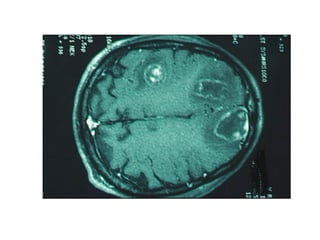

Question 8 27yo with HIV, CD4 ct 175, on daily TMP-SMX Seizure, weeks of stumbling Toxo serology (-) 2 years ago Head CT with 2 large parietal lesions with surrounding edema and midline shift

The best approach to management would be: A.  2 weeks of empiric therapy with TMP-SMX followed by repeat CT B.  2 weeks of empiric TMP-SMX + dexamethasone, followed by CT C.  CT-guided needle biopsy D.  LP to evaluate CSF for EBV PCR E.  Open brain biopsy

Question 8 (CSF for EBV PCR) CT-guided needle biopsy Select the most appropriate management for a patient with HIV and a CNS mass lesion.

Question 8 27yowith HIV, CD4 ct 175, on daily TMP-SMX Seizure, weeks of stumbling Toxo serology (-) 2 years ago Head CT with 2 large parietal lesions with surrounding edema and midline shift

The best approachto management would be: A. 2 weeks of empiric therapy with TMP-SMX followed by repeat CT B. 2 weeks of empiric TMP-SMX + dexamethasone, followed by CT C. CT-guided needle biopsy D. LP to evaluate CSF for EBV PCR E. Open brain biopsy

Question 8 (CSFfor EBV PCR) CT-guided needle biopsy Select the most appropriate management for a patient with HIV and a CNS mass lesion.